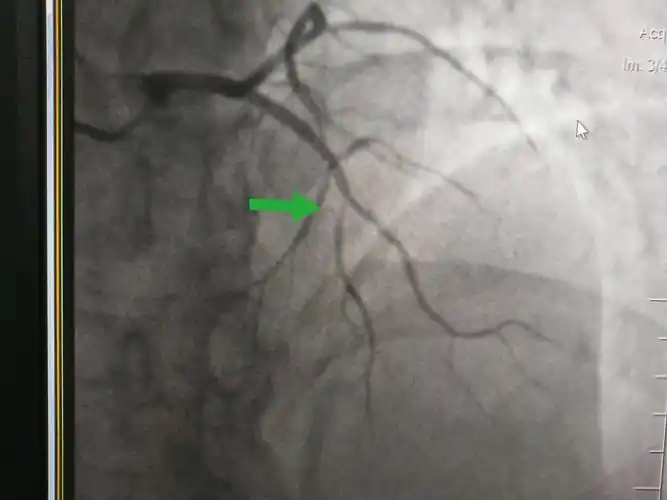

承德县医院内一科经皮冠状动脉造影支架植入术病例分享 - 美篇